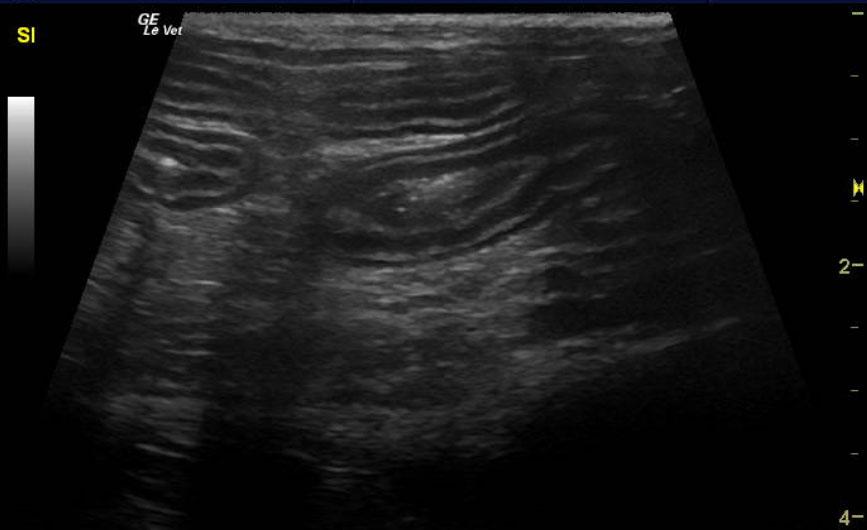

Image Interpretation

The spleen was enlarged and micronodular with slight scalloping contour. The spleen measured 1.33 cm. The mesenteric root lymph nodes were enlarged at 0.62 cm with reactive surrounding fat. Other mesenteric root lymph nodes measured 1.4 x 2.0 cm with reactive fat. Slight free fluid was noted owing to lymphatic strangulation. The remainder of the bowel revealed increased muscularis to mucosa thickening with a 2:1 ratio.